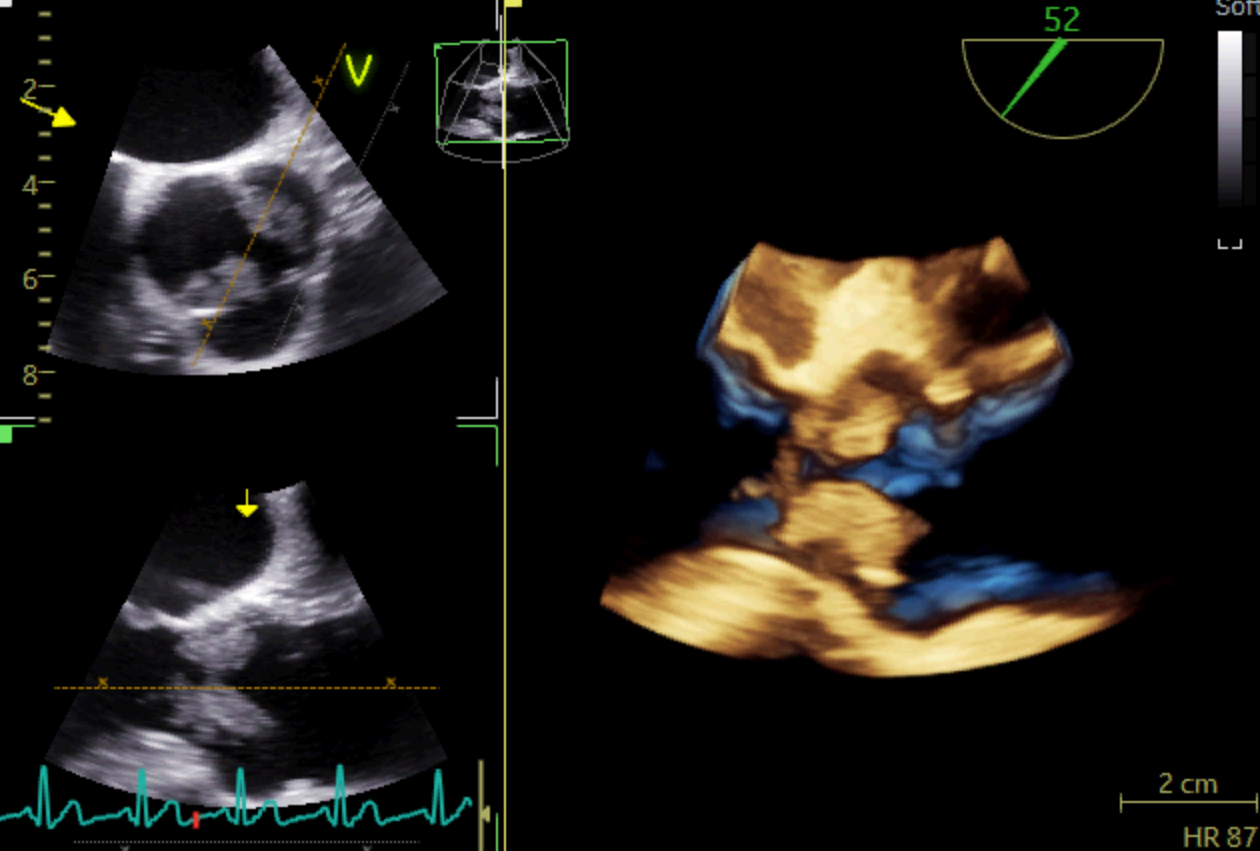

A 51 years-old man presented to the ED for dysarthria and left hemiparesis of sudden onset, dating back to approximately an hour. His past medical history included a deep venous thrombosis, currently under anticoagulant treatment, and a pancreatic cancer with hepatic metastases. Vital signs were normal and the physical examination was unremarkable except for the neurological part. The clinical suspicion of ischaemic stroke due to the occlusion of the internal left carotid artery was promptly confirmed through a CT scan and the patient successfully underwent a mechanical thrombectomy. The following day, to further investigate the nature of his thromboembolism, a TTE was performed: which surprisingly revealed two massive vegetations on the aortic and tricuspid valves. The subsequent TEE showed a circumferential three-cusp aortic involvement with a high-risk 18 mm-filamentous vegetation protruding into the left ventricular outflow tract; severe valvular insufficiency was also detected together with another large vegetation involving the subvalvular tricuspid apparatus. A total body CT-scan highlighted bilateral pulmonary embolism and splenic embolism, as further complications of the endocarditic process. During the stay the patient presented fever and blood exams were consistent with a diagnosis of sepsis; hence, upon the infectious disease specialist advice, he was started on a high-dose-ceftriaxone-and-vancomycin empirical antibiotic therapy. Eventually, blood cultures turned out negative. After a multidisciplinary meeting involving the core of the Endocarditis Team and the hospital oncologists, a conservative approach was chosen over the heart surgery, due to the patient’s critical conditions and poor prognosis. Therefore, he was transferred to the Oncology service to start palliative chemotherapy. Infective Endocarditis is frequently a difficult disease with non-specific systemic symptoms and late diagnosis; however, the onset can also be abrupt, with life-threatening complications, such as our patient’s. Multimodality imaging is key to make a prompt diagnosis of the disease and its complications and to timely plan the therapeutic strategy. A multidisciplinary management through a dedicated Endocarditis Team remains the mainstay to obtain the best clinical outcome.